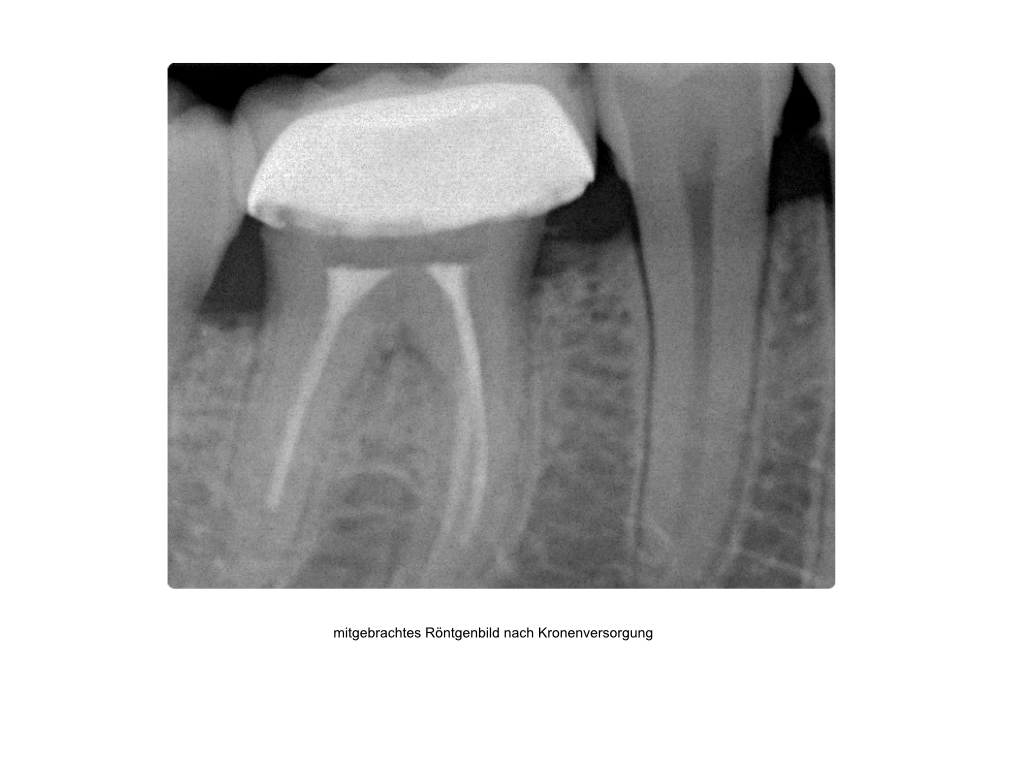

Saving hopeless teeth (36)